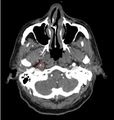

Evaluation

Denver screening criteria for blunt cerebrovascular injury

The Denver Screening Criteria are divided into risk factors and signs and symptoms

- Basilar Skull Fracture with carotid canal involvement